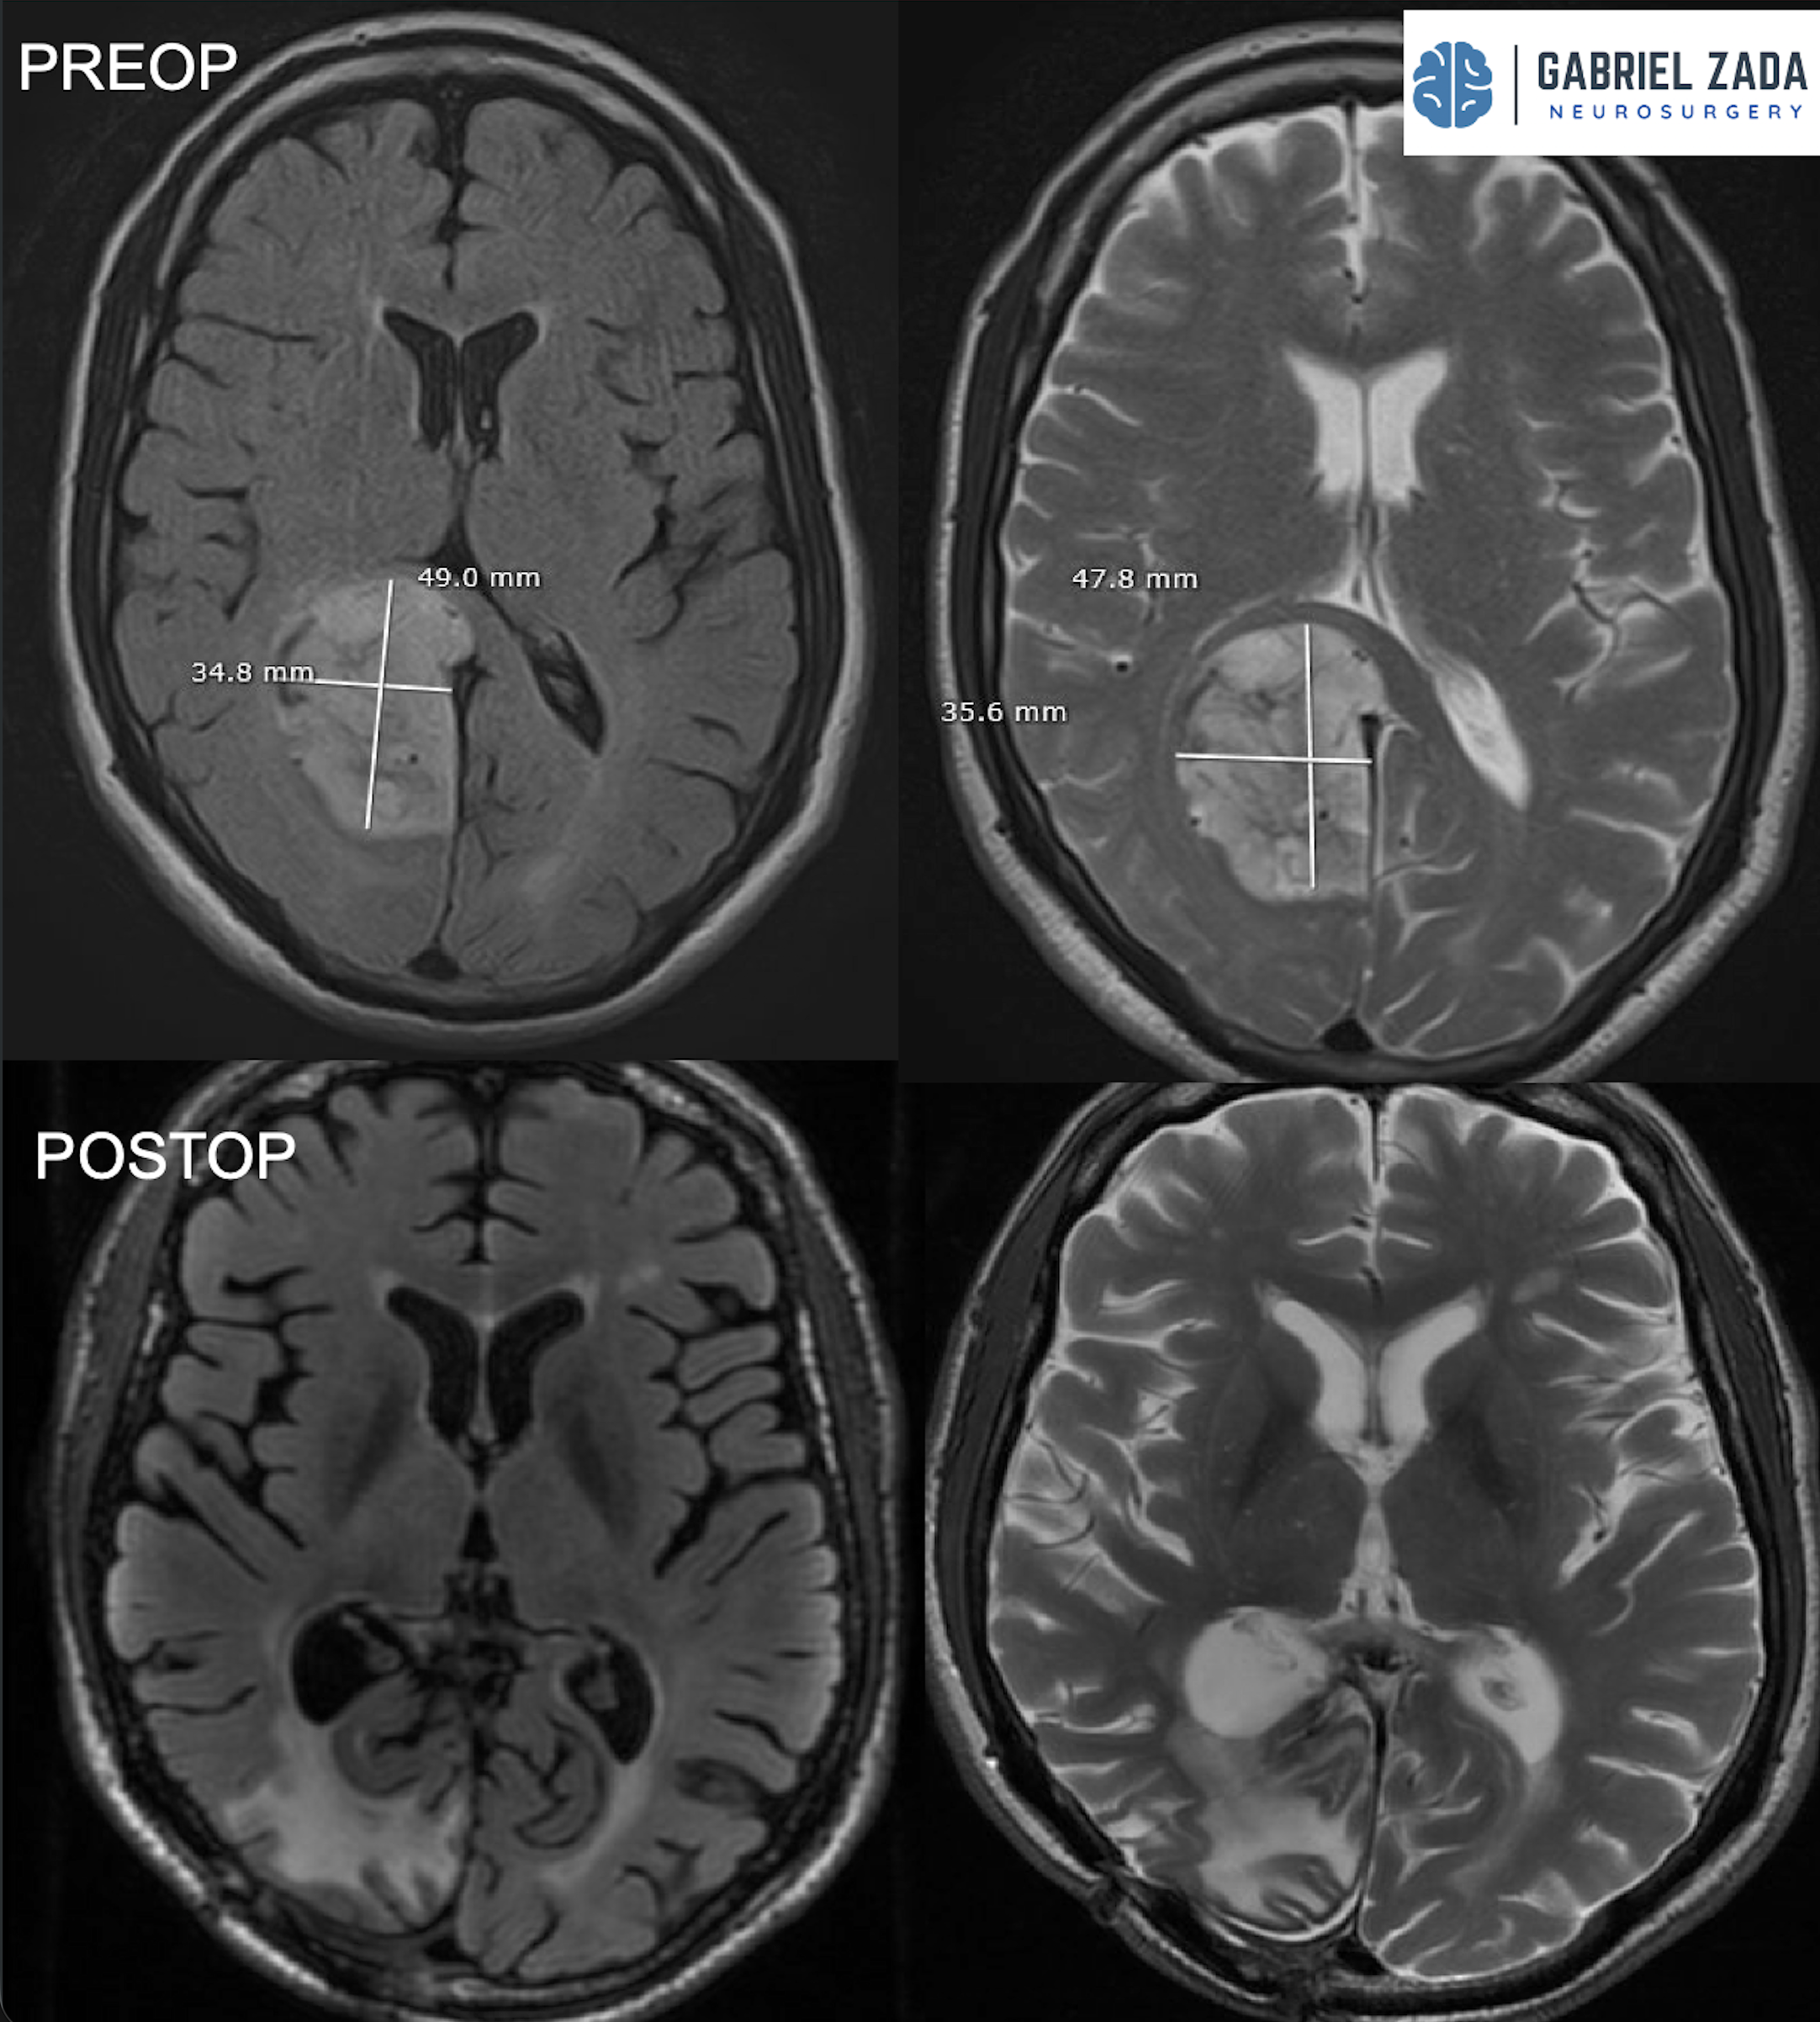

Explore this comprehensive gallery featuring pre‑ and post‑operative imaging of patients with skull‑base tumors treated by Gabriel Zada, MD, MS, FAANS, FACS. These cases highlight Dr. Zada’s expertise in advanced neurosurgical techniques and outcomes.

*Representative cases shown for educational purposes. All images de-identified. Individual results vary.